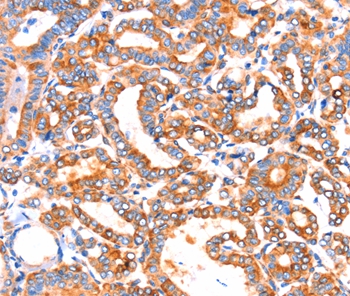

IHC (Immunohistochemistry)

(The image on the left is immunohistochemistry of paraffin-embedded Human liver cancer tissue using AAA240795(SEPT4 Antibody) at dilution 1/50, on the right is treated with synthetic peptide. (Original magnification: ×200))